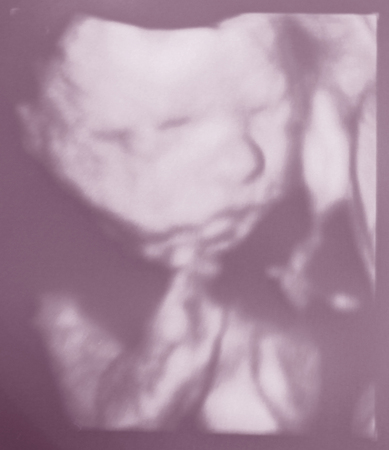

А вот драгоценные три фоточки тефтельки:

3. А тут он кулачок разжал))) Не могу наглядеться на него)))